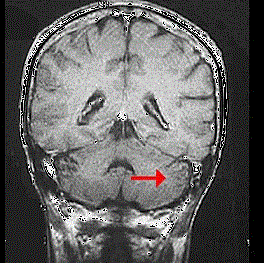

如图箭头所示为大脑哪个部位 ( ) A、脑干B、额叶C、枕叶D、小脑E、顶叶

问题 如图箭头所示为大脑哪个部位 ( )

选项 A、脑干 B、额叶 C、枕叶 D、小脑 E、顶叶

答案 D